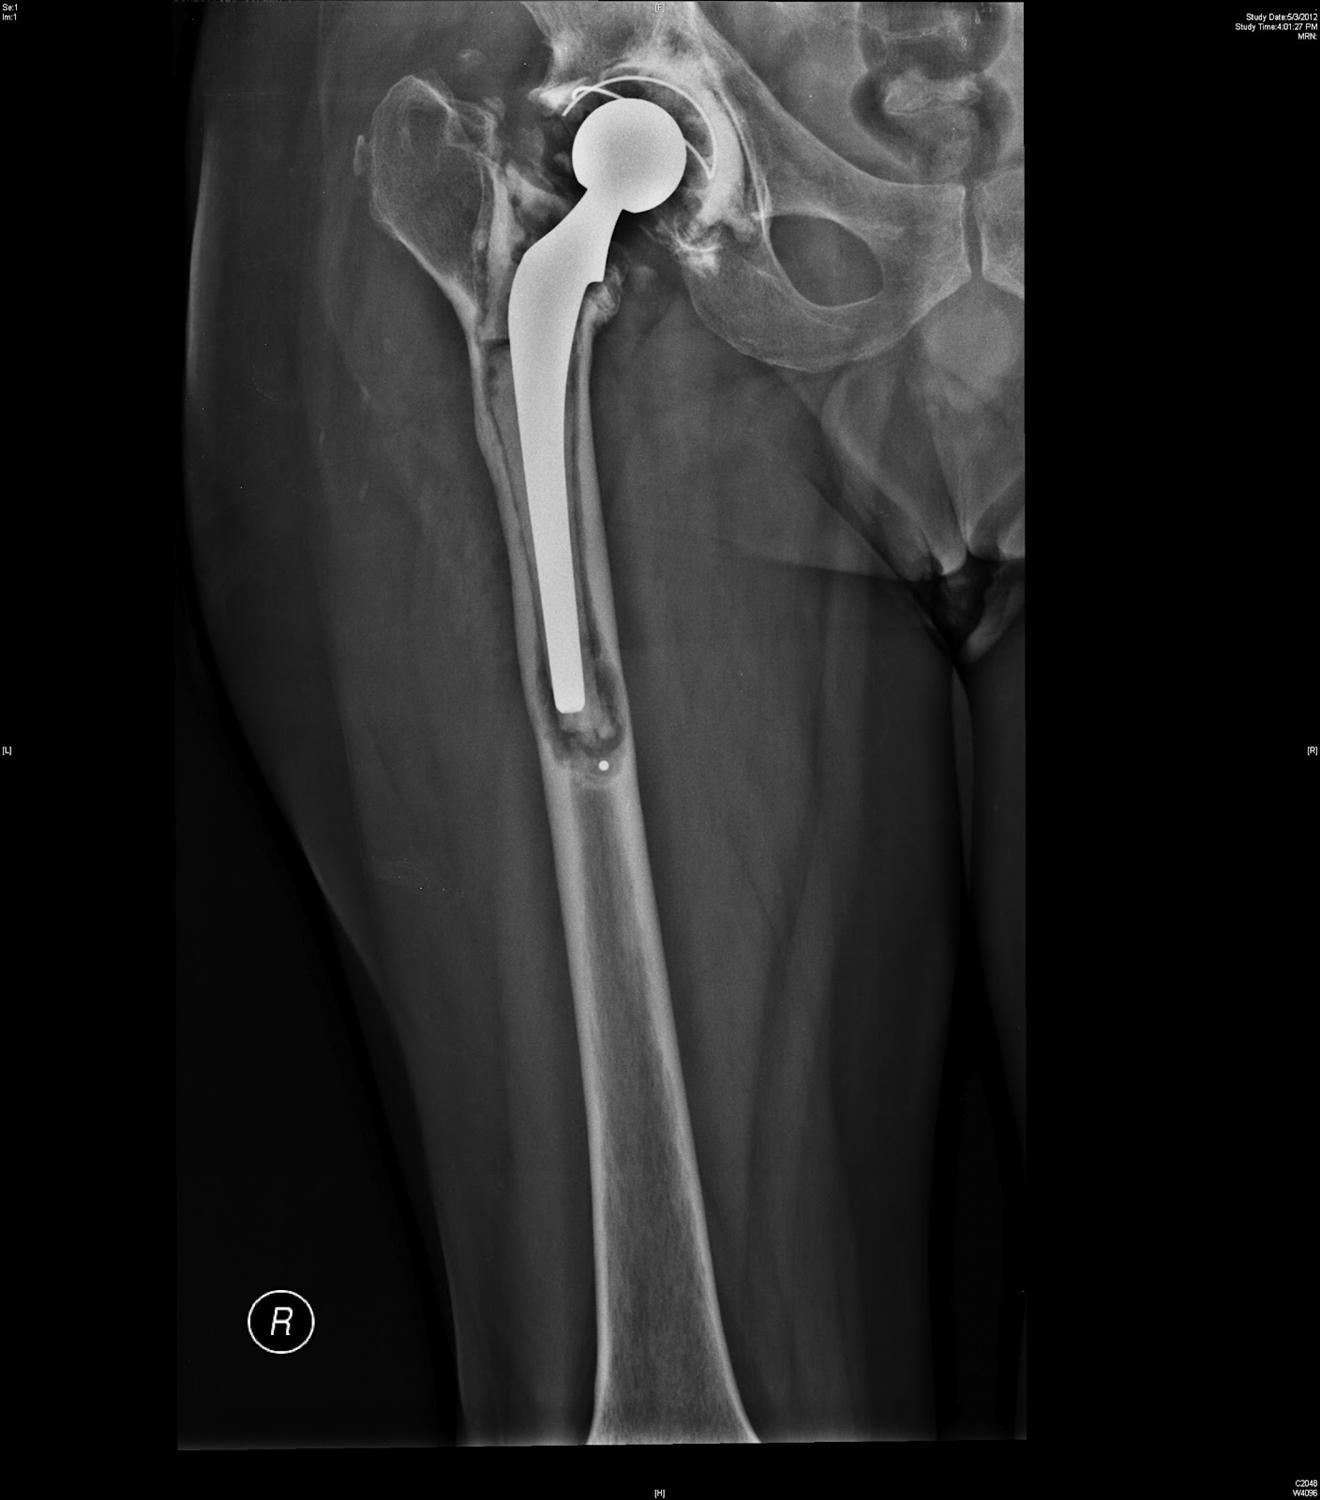

Lateral radiograph of the right total hip arthroplasty. Download Cemented Hip Replacement Xray Interactive cases are presented in the menubar to test your. When cemented, a plastic medullary cavity plug may be used to stop the inferior migration of the cement. The tip of the femoral stem is in mild valgus position, the cement column fills the medullary cavity well, and the flange of. The femoral stem is cemented; Image from a patient. Cemented Hip Replacement Xray.

(a) Type B2 periprosthetic femoral fracture around cemented polished Cemented Hip Replacement Xray Hip arthroplasty is one of the most common procedures performed for the treatment of advanced osteoarthritis and is also a. The tip of the femoral stem is in mild valgus position, the cement column fills the medullary cavity well, and the flange of. Image from a patient who had a normal total hip arthroplasty. In a total hip replacement (also. Cemented Hip Replacement Xray.